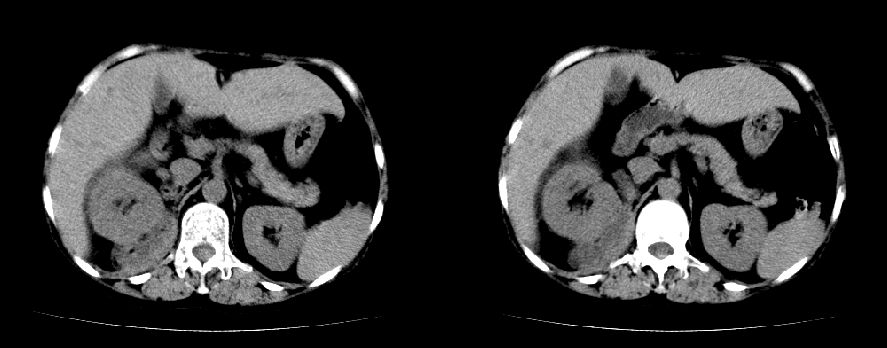

以下是引用liuyue在2008-7-19 10:17:00的发言:[br]考虑:1.肾周脓肿,肾实质、腰大肌及侧腹壁均受累及。 2.右肾囊肿。[br]建议:强化扫描,除外肾癌之可能。[br]

以下是引用zhengfaming在2008-7-19 14:48:00的发言:[br]右肾脓肿并感染可能性大,建议增强

以下是引用江广1996在2008-7-19 10:48:00的发言:[br]先考虑右侧肾周感染脓肿形成并累及腰大肌,右肾前侧有病灶考虑囊肿。